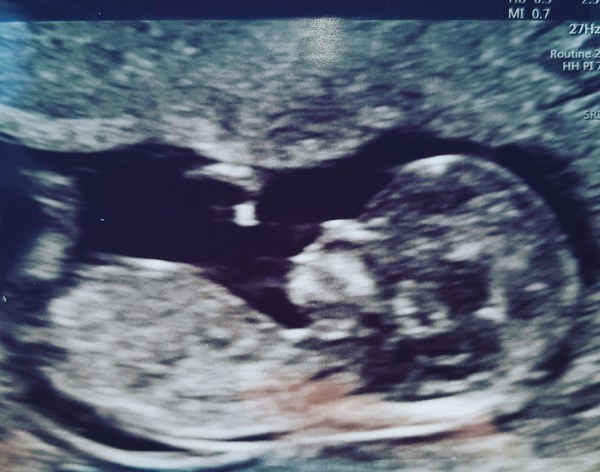

Just had our scan and measuring 12+2 so due date is 11th December. All looked well and can't believe how much little one has grown in less than 2 weeks!

December 2018 Babies - Thread #2

Great picture Tea. Mine was hopping about so much was hard to get a good profile but all looked good! My big belly possibly got in the way too!

Wow, what a great picture!

Awww beautiful picture!!

Congratulations @MrsTeaPlease ! Looks totally beautiful!